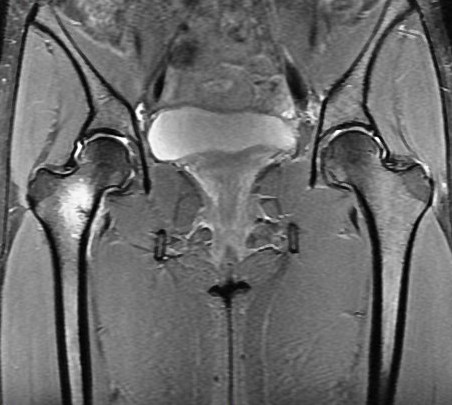

Figure 4 for case Calcar stress fracture ( RID4695 )

Figure 4